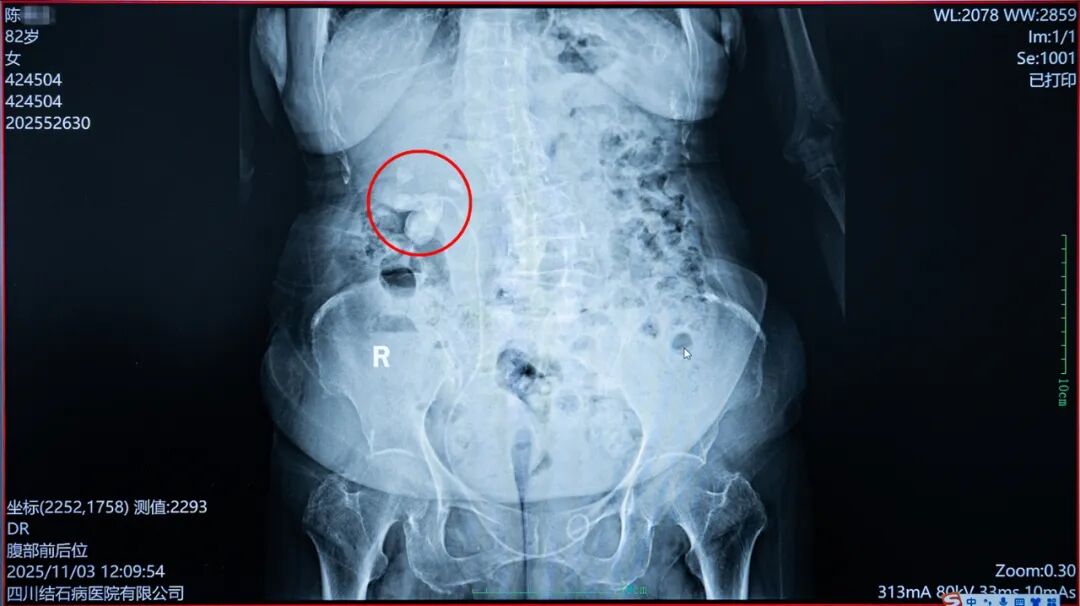

看着患者的检查报告,国际尿石症联盟IAU委员、四川十大外科名医、四川结石病医院泌尿外科带头人常立高教授判断,感染的元凶正是右侧肾脏内的那颗铸型结石。结石造成了尿路梗阻,尿液无法正常排出,导致肾积水日益加重,继而引发肾脏及周围组织严重感染。

△ 患者右肾内的结石